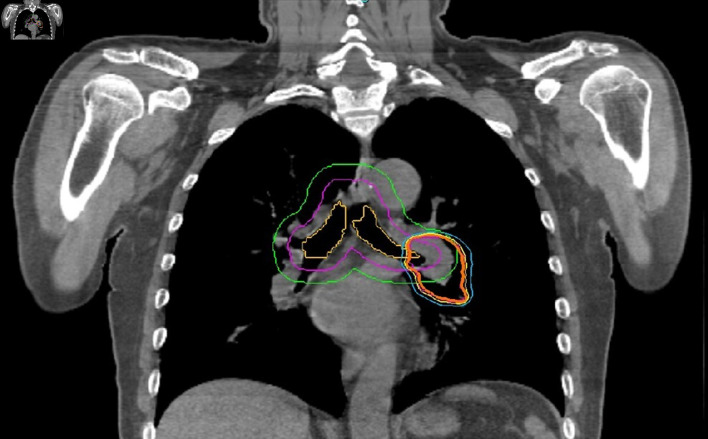

Methods: Forty-two lesions from 35 patients were treated between 2019 and 2022. Four-dimensional computed tomography images were obtained when the patients were in a free breathing modality. Tracking modality was selected prospectively according to the visibility of the target. The median prescribed dose was 48 Gy in four fractions (fx) (28 - 55 Gy/1- 7 fx). The median age was 68 years (47 - 82 years), and 43% of cases were adenocarcinoma. The median lesion size was 15 mm (6 - 36 mm).

Results: Complete, partial and stable responses were obtained as 26%, 62%, and 9.5% at a median of 2 months (1 - 6 months), and 35.5%, 47.5% and 5% at the 12th month evaluation, respectively. Grade 3 and higher toxicity was not observed in any case. The mean and 2-year overall survival (OS) was 31.5 months and 54%, and the local recurrence-free survival (LRFS) was 29.6 months and 51%, respectively. In univariate analysis, target lesion type, complete response (CR), and higher esophagus maximum dose were favorable factors for OS and LRFS (P < 0.05). The CR at 12th month evaluation remained significant in multivariate analysis in terms of OS (hazard ratio = 8.602, 95% confidence interval: 1.05 - 70.01; P = 0.044).

Conclusions: A mean LRFS of 29.6 months and OS of 31.5 months were obtained in patients with primary and metastatic lung cancer. With a median treatment time of 25 min, motion-managed strategy with CK-M6-LOT-based SBRT is an effective, safe, and comfortable treatment method for lung cancer.